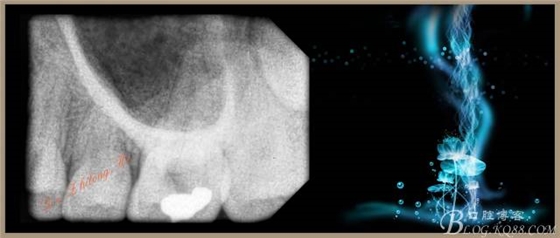

檢查:#26PO可見(jiàn)大面積黑色充填物,腭側(cè)充填物脫落少許,缺損深及髓腔,探(+++),叩(-),冷試驗(yàn)敏感。X-ray示PO充填物近髓腔,根尖周無(wú)明顯異常。

2、手用#15K銼疏通根管+測(cè)量WL:P19.5mm,DB、MB、MB217mm。